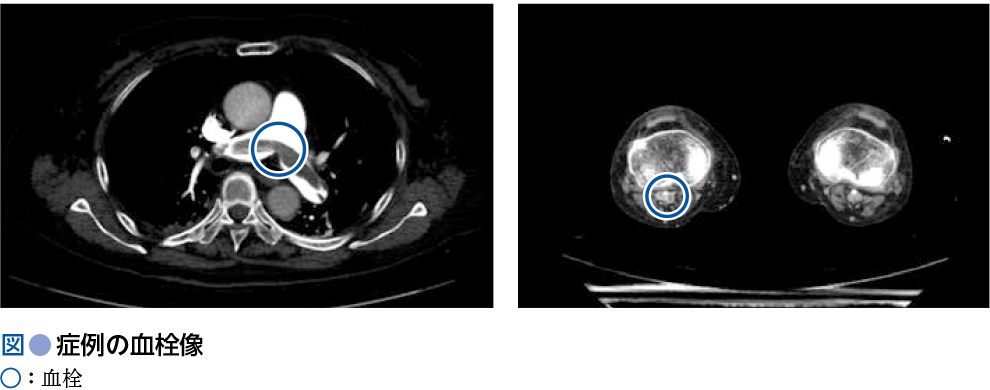

日中起立時の突然の呼吸困難:初診時 初診時 68歳女性.肺癌術後で経過観察をしている.多発神経炎に対してステロイドを内服している.日中は坐位で過ごすことが多い.日中起立時に突然の呼吸困難が出現し,救急車で来院した. 来院時,意識清明,血圧96/71 mmHg,脈拍98回/分,呼吸回数26回/分,SpO2 95%(O2 10 L/分リザーバーマスク)であった.来院時採血では,トロポニンT 0.168 pg/mL,FDP 29.3μg/mL,Dダイマー12.21μg/mL,eGFR 44 mL/分/1.73 m2であった.心エコーでは左室のD-shape様変形を認め,右室の拡大を認めた.造影CT検査を施行したところ以下の通りであった. ※クリック/タップで拡大します 本症例の診断は何か.2つ選べ. ⓐ肺血栓塞栓症 ⓑ急性心不全 ⓒ急性心筋梗塞 ⓓ深部静脈血栓症 本症例に対する初期治療薬として,適切でないものはどれか. ⓐアスピリン ⓑ直接作用型経口抗凝固薬(DOAC) ⓒ未分画ヘパリンナトリウム ⓓワルファリン A1 ⓐ肺血栓塞栓症,ⓓ深部静脈血栓症A2 ⓐアスピリン 重症度評価に基づく治療方針の選択 造影CT上肺動脈主幹部に血栓像があり,右膝窩静脈-大腿静脈に血栓像を認め,肺血栓塞栓症および深部静脈血栓症と診断される(図). 血行動態は保たれているものの,簡易版PESI≧1(表1),右室機能不全と心筋逸脱酵素の上昇を認め,重症度クラスは中[高]リスク(表2)に該当する. 中[高]リスクの症例に対しては,抗凝固療法を第一選択とするが,経過中に血行動態が不安定化する可能性に注意し慎重なモニタリングを要する.血行動態の悪化時は血栓溶解療法を考慮する. 現在のガイドライン1)上,血栓溶解療法の適応は,ショックや低血圧が遷延した重症例のみである.モンテプラーゼ(点滴静注:13,750~27,500単位 /kg,2分間で静注)が使用可能である. ワルファリンを投与する場合は,投与開始から治療域にコントロールされるまで未分画ヘパリンナトリウムを併用する. DOACは即効性があり(抗凝固作用の発現まで1〜4時間程度),ショックのない症例では通常DOACが第一選択として使用されることが多い. 経過観察中に血栓溶解療法を使用する可能性が高いと予想される症例では,半減期が1時間と短い未分画ヘパリンナトリウムが使用しやすい. 文 献 日本循環器学会,他:肺血栓塞栓症および深部静脈血栓症の診断,治療,予防に関するガイドライン(2017年改訂版)(2021年11月閲覧) Konstantinides SV, et al:2014 ESC guidelines on the diagnosis and management of acute pulmonary embolism. Eur Heart J, 35:3033-3069, 3069a, 2014 (2022/06/03公開) 戻る この"ドリル"の掲載書をご紹介します 循環器薬ドリル 薬剤選択と投与後のフォローも身につく症例問題集 池田隆徳/監,阿古潤哉/編 定価:4,950円(本体4,500円+税) 在庫:あり 月刊レジデントノート 最新号 次号案内 バックナンバー 連載一覧 定期購読案内 定期購読WEB版サービス 定期購読申込状況 レジデントノート増刊 最新号 次号案内 バックナンバー 定期購読案内 residentnote @Yodosha_RN その他の羊土社のページ ウェブGノート 実験医学online 教科書・サブテキスト 広告出稿をお考えの方へ 広告出稿の案内